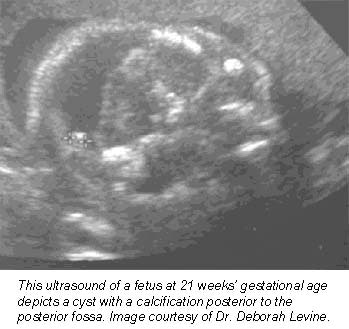

An example of MRI’s newfound obstetric niche can be found at New York City’s Mount Sinai School of Medicine, where radiologists often use the modality to better image cranial masses that are difficult to diagnose solely with ultrasound, according to a report presented at the 2001 American Institute of Ultrasound in Medicine meeting.

Still more applications are being pioneered at Boston’s Beth Israel Deaconess Medical Center, where researchers are nearing the end of a five-year study funded by the National Institutes of Health to evaluate how MRI complements prenatal ultrasound in the diagnosis of central nervous system disorders. So far, their results are promising.

"MR almost always will make you more sure of your diagnosis," said associate professor of radiology Dr. Deborah Levine. "It informs how we counsel the patient. Sometimes it directs the mode and timing of delivery, or helps a patient decide whether to terminate a pregnancy."

Levine, who oversees about one prenatal MRI exam per week, said she finds the modality especially helpful in determining whether fetuses suffer from central nervous system anomalies, as well as for defining many chest masses. Some radiologists are also using MRI to get a better idea of fetal volume, particularly in abnormal fetuses that are either too large or too small, she said.

Basically, MR is helpful whenever ultrasound is unclear, Levine said -- a general rule of thumb that’s allowed the procedure to catch on at institutions nationwide.